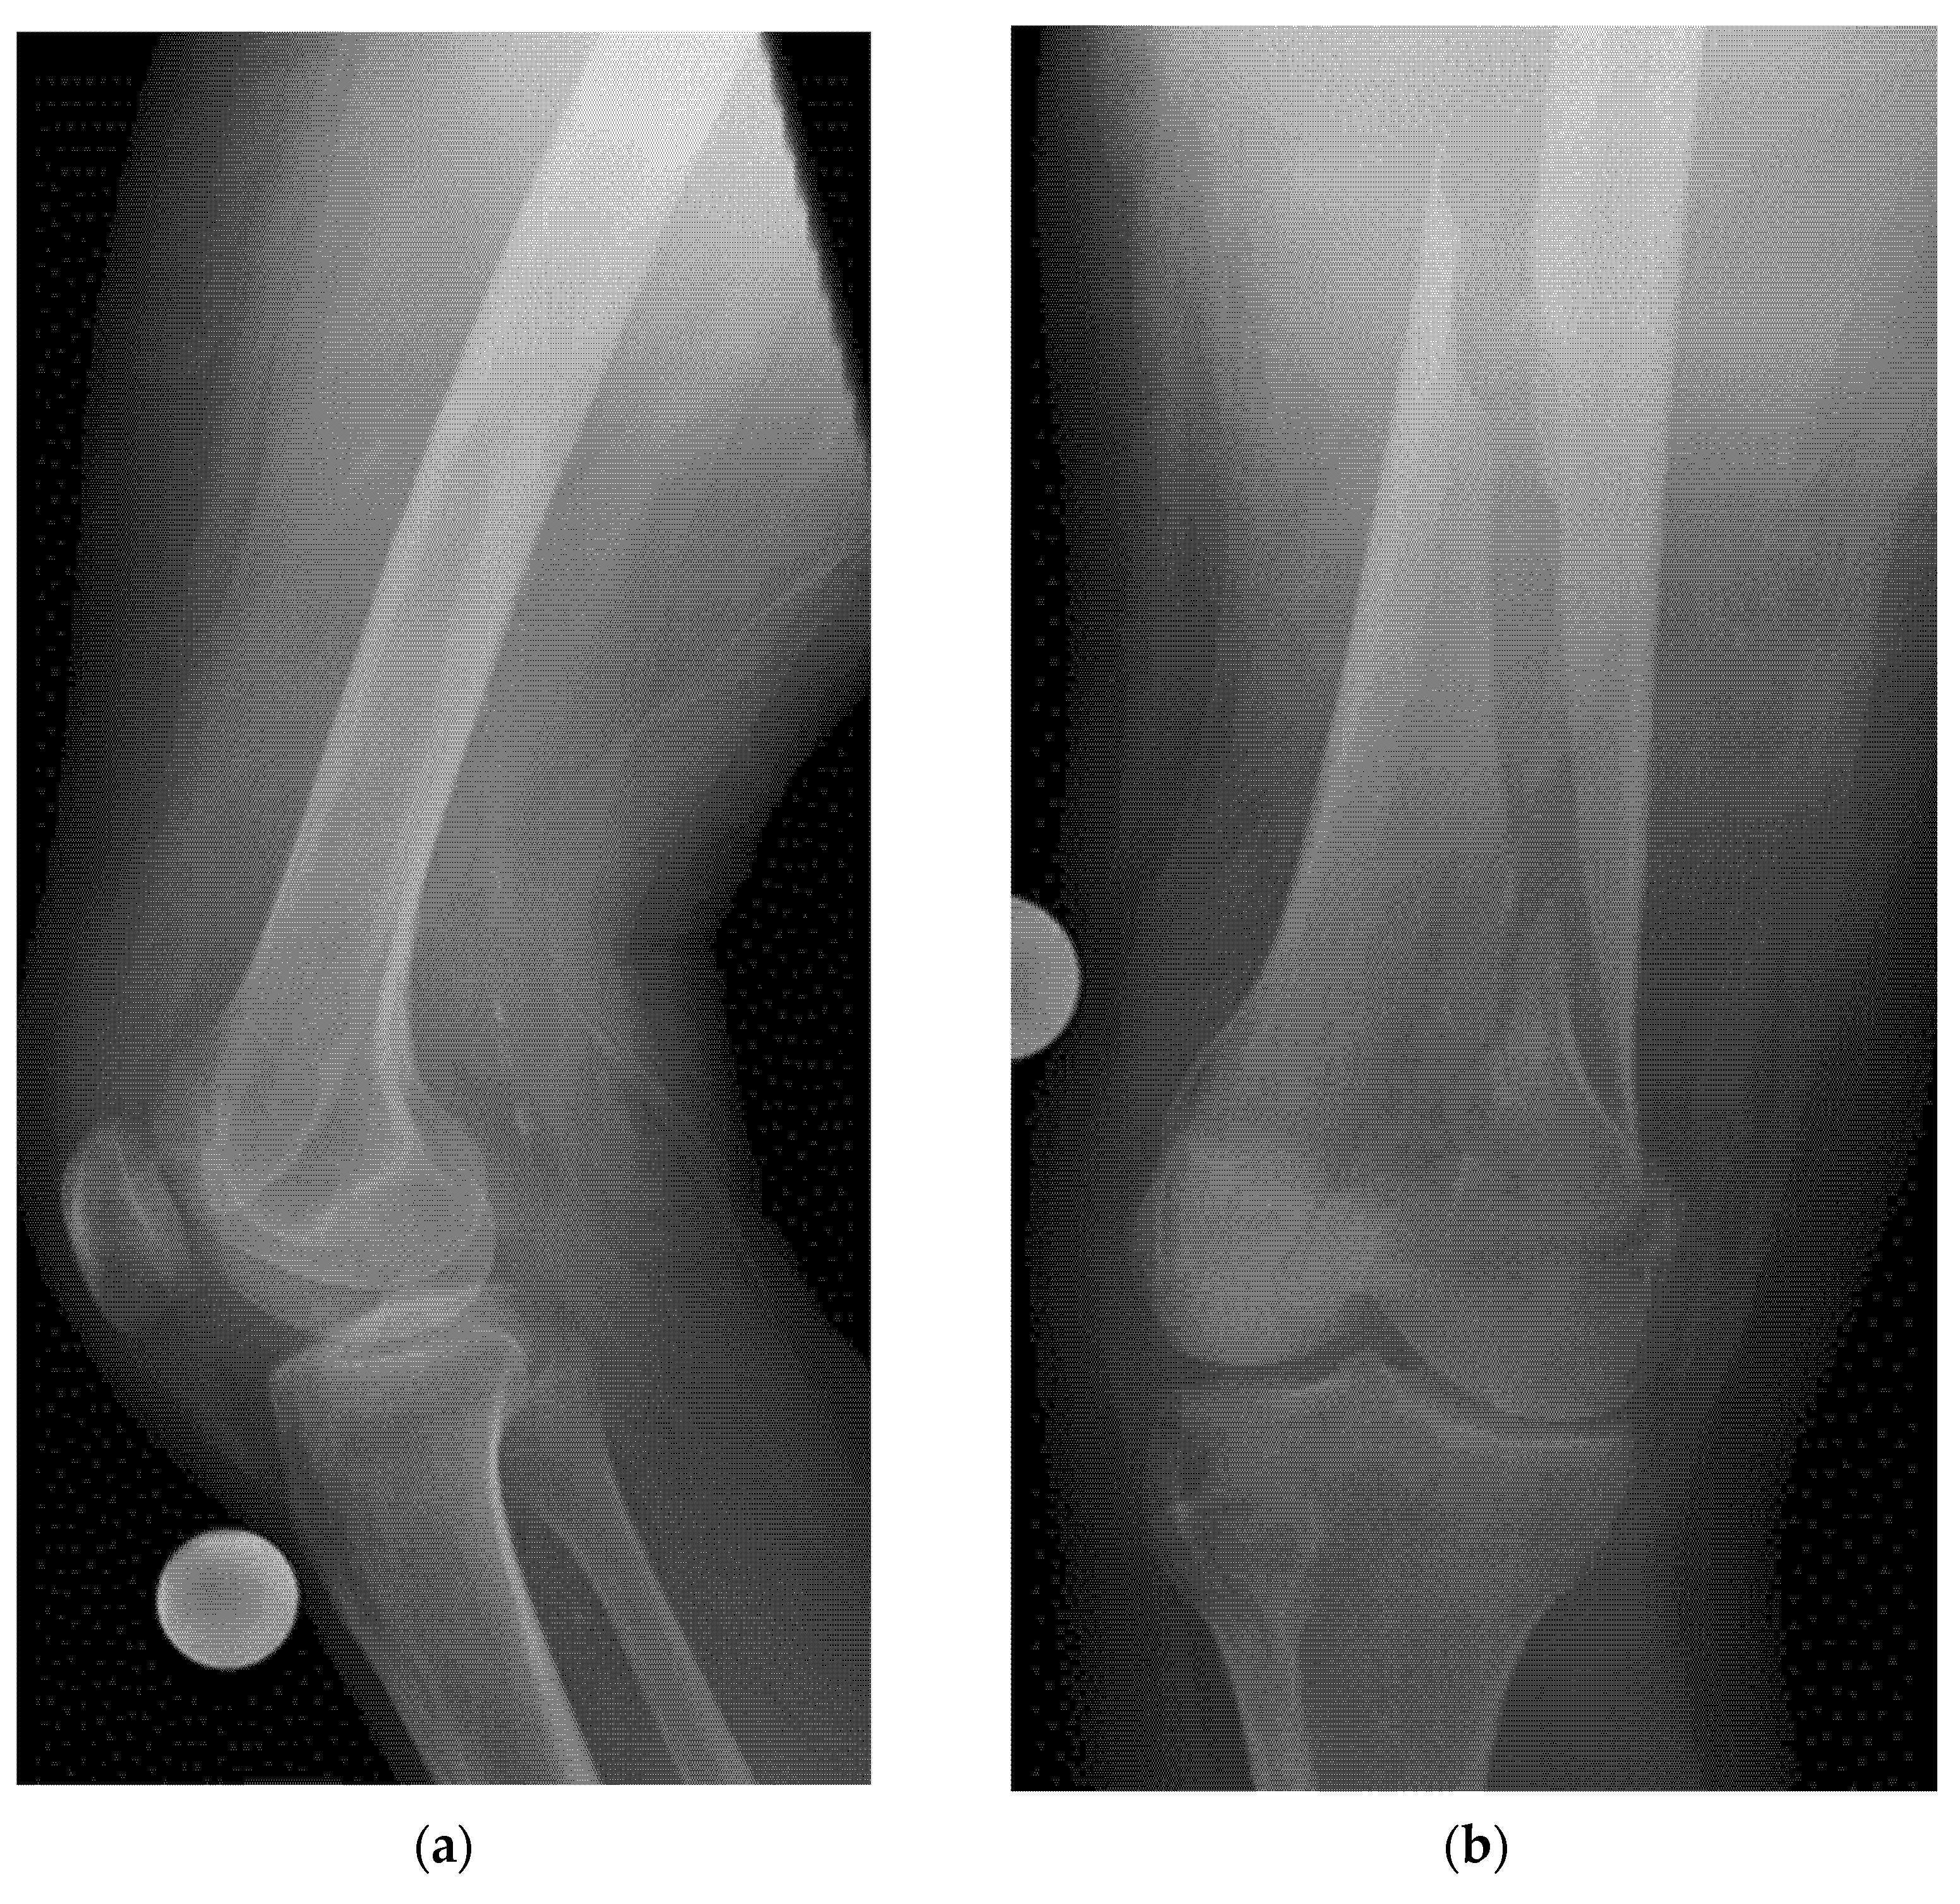

- Example: Suspected left shoulder dislocation